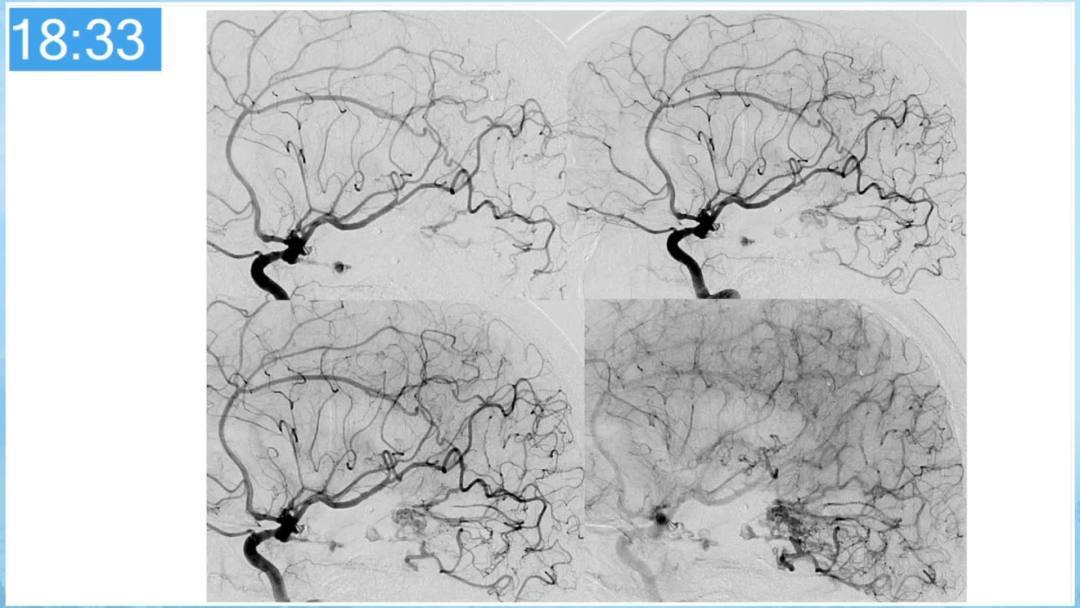

合理的复合平台下的综合治疗,针对每一个病变对应不同方法安全性分析,不预设、不排斥,每种技术发挥到最佳,互相保障。